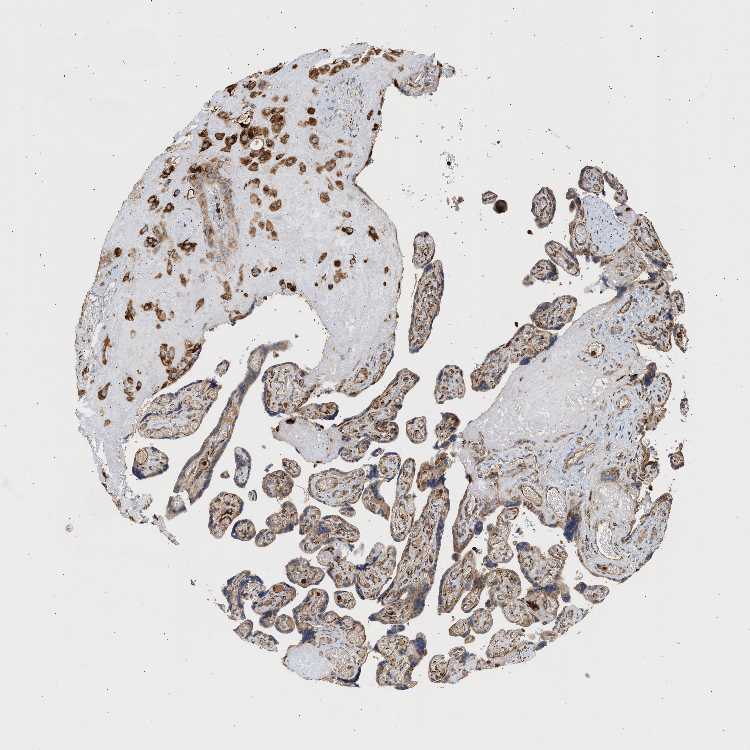

TISSUE PRIMARY DATA PLACENTA Show tissue menu

PLACENTA - Antibody stainingi

Antibody staining in the annotated cell types in the current human tissue is reported as not detected, low, medium, or high, based on conventional immunohistochemistry profiling in selected tissues. This score is based on the combination of the staining intensity and fraction of stained cells.

Each image is clickable and will lead to virtual microscopy that enables deeper exploration of all samples and also displays staining intensity scores, fraction scores and subcellular localization as well as patient and tissue information for each sample.

Antibody HPA020107Antibody HPA021677Antibody CAB009913

Decidual cells HighHighMedium

Trophoblastic cells MediumMediumMedium